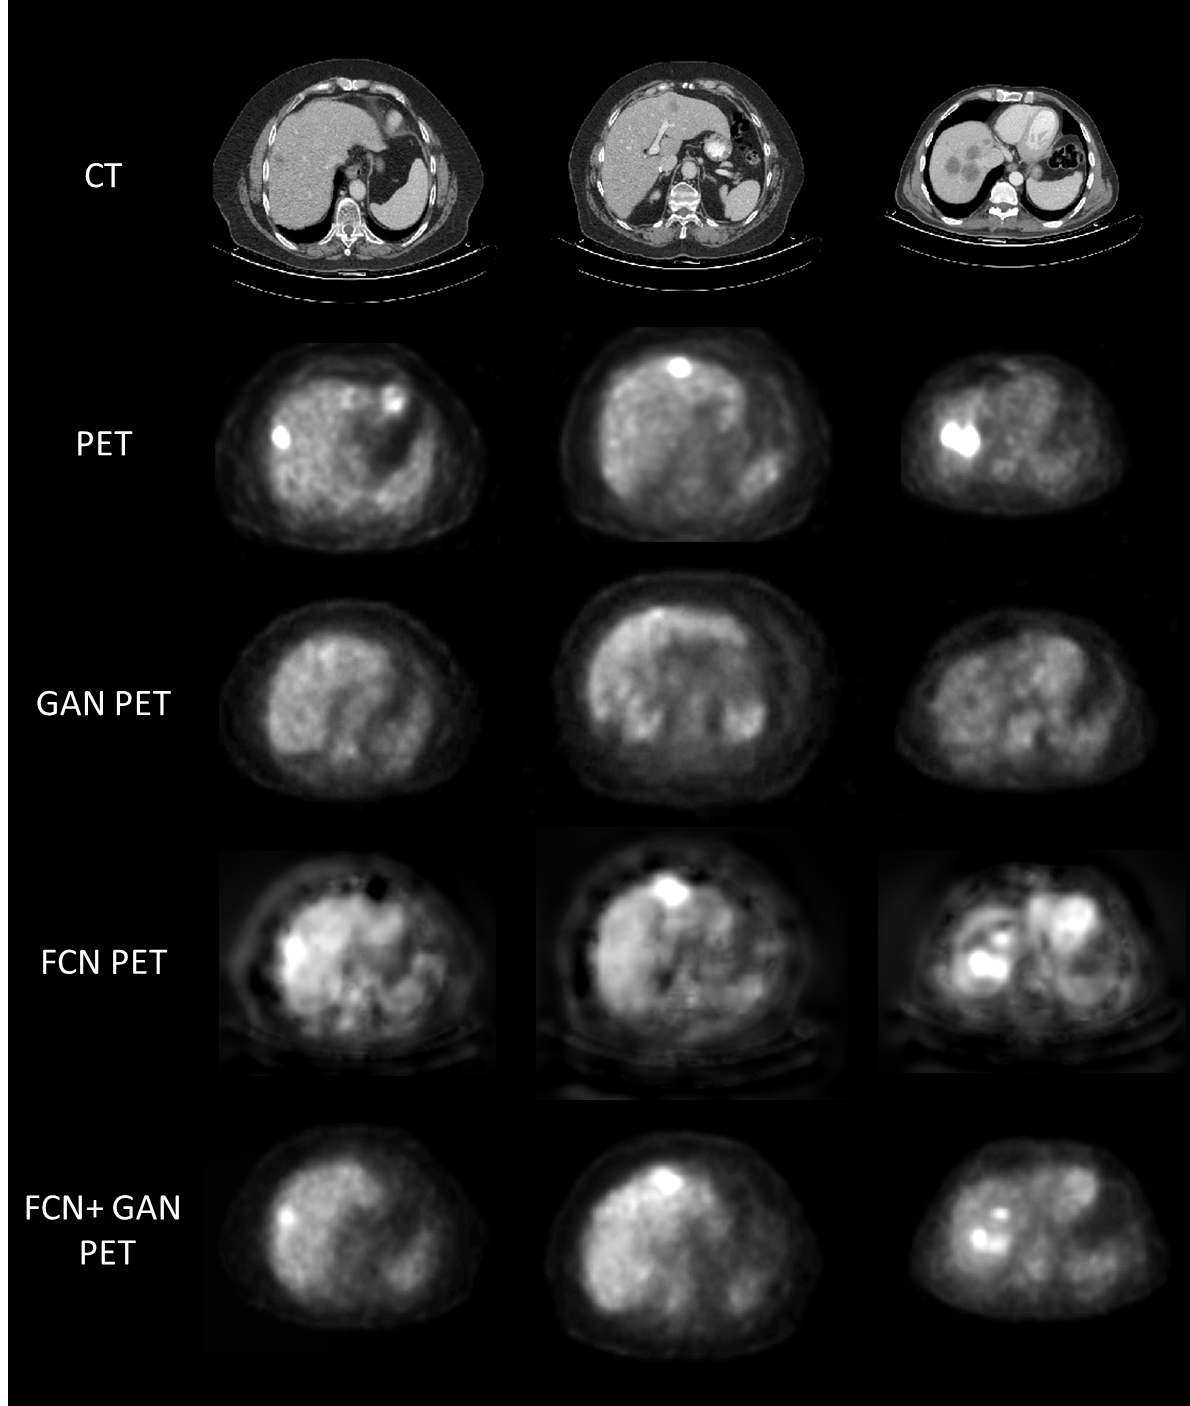

Figure 4: Sample results of the predicted PET using FCN and conditional GAN compared to the real PET.

The testing set included 8 CT scans with a total of 26 liver tumors. The corresponding PET scans were used as comparison with the predicted virtual PET. Our FCN and GANs based system successfully detected 24 out of 26 tumors (TPR of 92.3%) with only 2 false positives for all 8 scans (average FPR of 0.25).

Fig. 4 shows sample results obtained using the FCN, and FCN blended with the conditional GAN, compared to the real PET scan. False positive examples are shown in Fig. 5. In these cases, the FCN mistranslated hypodense regions in the liver to high SUV values.